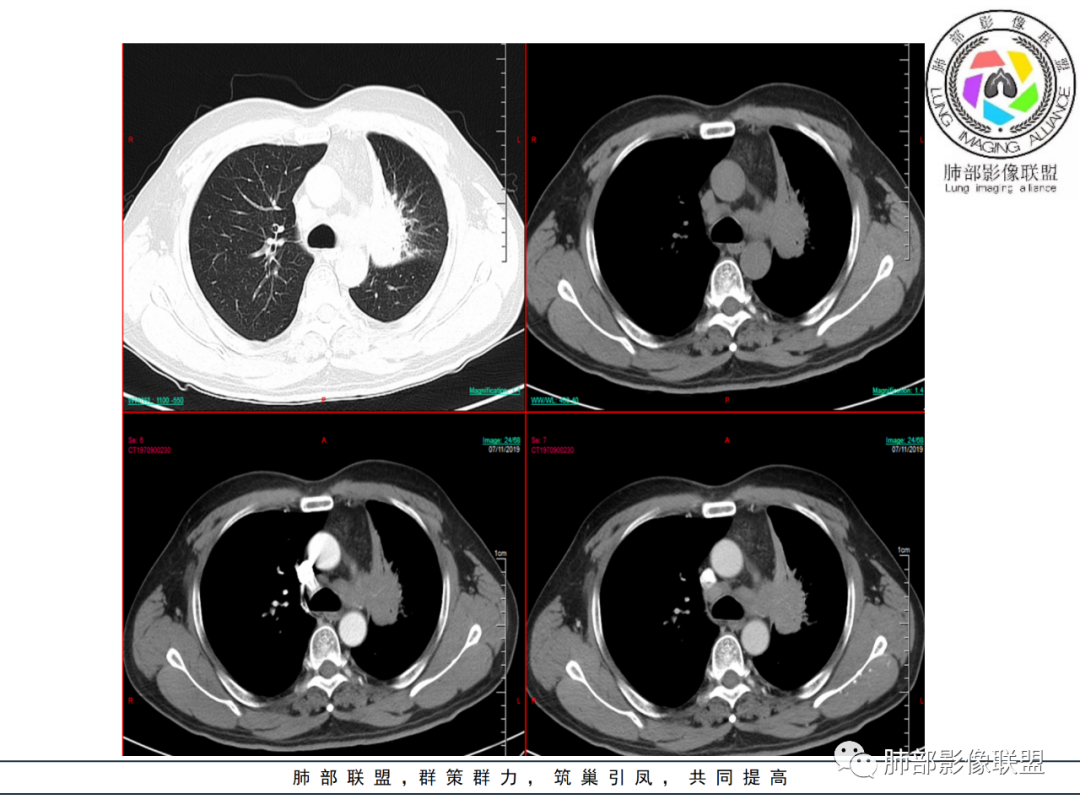

再就是淋巴结肿大的形态,而且坏死不明显,大多是保持了椭圆形,符合炎性增生改变,不符合肿瘤淋巴结转移的改变。还有临床症状,咳嗽,咳痰一个月。也支持慢性炎症。 医学百科网 | YxBaike.Com

为啥强化完,感觉看不出来肿瘤的边界啊,为啥强化的这么均匀啊为啥管腔管壁这么清楚啊,为啥淋巴结还都肿大融合了 医学百科网 | YxBaike.Com

强化均匀,延迟强化,还有支气管多支受累似乎,部分狭窄后又通了,远端多支气管壁厚

没有明确肿块,强化大致都是均匀的,所以不太考虑肿瘤,除非淋巴瘤,淋巴瘤对我来说掌握的太少,放一放,所以炎性病变可能 医学百科网 | YxBaike.Com

这个血管是均匀受压,光滑,也不太支持肿瘤;好像淋巴瘤还真有可能

面积太大了,周围还有一些模糊晕样表现,强化太明显太均匀了。而且临床有胸闷,一过性。说明支气管偶尔有通而不畅表现。

鼠尾状狭窄,远端堵塞,多考虑癌,但是狭窄后扩张,自然结核要考虑 医学百科网 | YxBaike.Com

强化太均匀了,没看到肿块

目测强化CT值不超过30,强化很弱啊

仔细看延迟期淋巴结内有坏死,结核还真要考虑了 医学百科网 | YxBaike.Com

这些淋巴结融合,中心低密度坏死,为结核的特点

我就想看支气管壁的破坏情况,但是不是很清楚,尖后段支气管远端似乎堵了,但好像又有穿出来,如果有穿出来就是狭窄后扩张,那肯定是结核的特点;肺门区前段和舌段的支气管就符合结核的特点:狭窄后扩张。 医学百科网 | YxBaike.Com